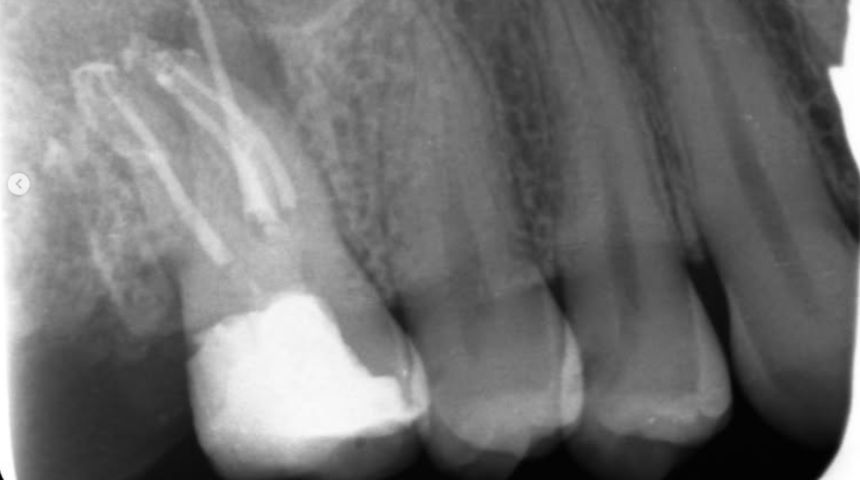

Take a look at some of our recent cases below!